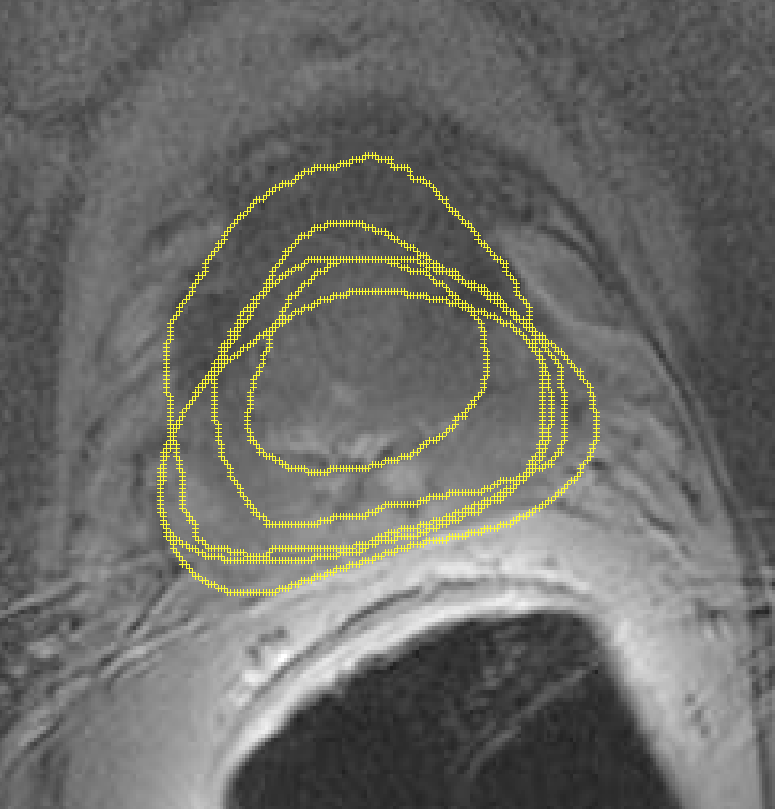

In the previous section, we simulated images in order to exploit “perfect segments”. In this section, we validate our approach using actual MR images of prostates. The image data from 15 patients were manually delineated by 5 oncologists.

The MR images used in this study were derived from an online database444http://prostatemrimagedatabase.com/. The database contains T2-weighted MR volume datasets, provided by Brigham and Women’s Hospital, the National Center for Image-guided Therapy, and Harvard Medical School. The images comprised T2-weighted MR images (T2W-MR) with endorectal coils. The pulse-sequence groups in the DICOM headers of most of the T2-weighted images were marked fast-spin echo (FSE), although some were marked as fast-relaxation fast-spin echo-accelerated (FRFSE-XL). The dataset contained images with slice thickness ranging from 2.5mm to 4.0mm, and varying contrast levels and signal-to-noise characteristics. All of the images were captured at a depth of 16 bits, and they varied in size from 256256 to 512512 pixels.

Sample images are depicted in Figure 6 (top row). Generally, one assumes that prostate segmentation is a relatively easy task. However, the variability of such segmentation remains considerable, and this is conspicuous in Figure 6 (bottom row).

We randomly selected 15 patients (out of more than 100) with a total of 558 slices, from which 145 slices were contoured by all 5 oncologists, resulting in a total of 725 segments555All DICOM images and their manual segmentations were provided by Segasist Technologies, Waterloo, ON, Canada.. Similar to the validation using simulated images, we first ran STAPLE on all user segments to generate a consensus for each slice. (Note that this is a “regular” consensus, insofar as all experts were available to mark the same image.) After we have the regular consensus, we can measure the agreement of each user using this consensus. This basically measures the extent to which each user has contributed to the consensus for that image. Table VII reports the results. From these results, User 3 is the most accurate666Theoretically, it is possible for four bad users to dominate the consensus, such that the fifth (excellent) user is understood as the worst. This is another reason to favor a large number of experts when building a consensus.. We selected User 3 as the gold standard. Then, we eliminated the segments from User 3 when building the atlas, in order to measure the accuracy of the computed consensus contours by comparing it against the manual delineations from User 3.

Barcode of images versus barcode of ROIs – The only difference between the experiments that used synthetic images and those that used real MR images was the manner by which the barcodes were calculated. In the case of synthetic images, most of the image area was relevant to encoding the prostate gland. In the MR images, by contrast, much more information is depicted, and the barcode loses its expressiveness when calculating the entire image. We assumed that when a user requests a consensus contour (as a second opinion or “peer review”, as it were) that user must have either already delineated the prostate, or at least drawn a rectangle around the ROI. That way, we can easily extract the barcode for the prostate region. Furthermore, we enlarged the dimensions of the bounding box constructed around each user’s segment by pixels (cm) to capture some of the structures around the prostate gland.